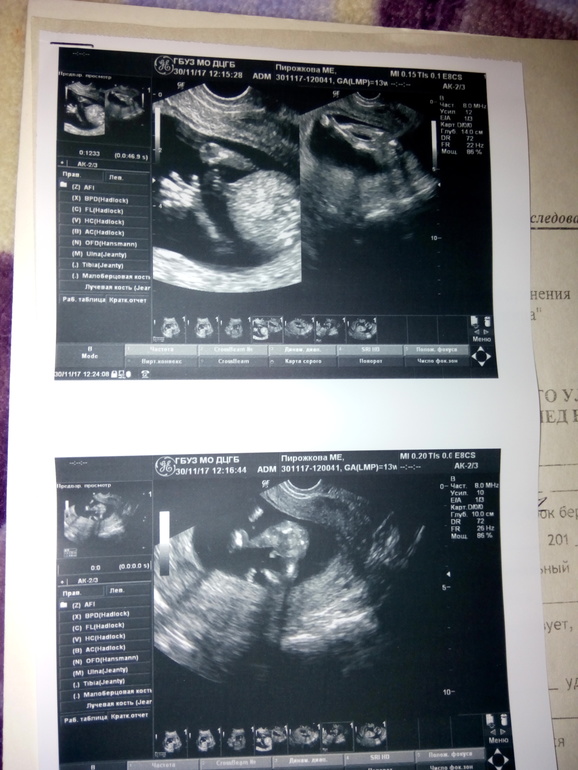

УЗИ, КТГ, доплерСижу на больничном с токсикозом, сказали моча в порядке, капельницы можно не делать, но от больничного не отказалась, так как состояние нестояния, слюни и рвота 2-5 раз в день продолжается. Но это все мелочи жизни, когда в животике живет Счастье))) Предложили сегодня внеплановое УЗИ, посмотреть пол, ну я и не стала отказываться. Сказали............ мальчик, по поведению мальчики ленивее девочек на узи, меньше пляшут, больше спят))) Ну а потом удалось впоймать откровенный ракурс. Девочки,знающие, у нас и правда похоже на мальчика? Мы настроились на Глеба Игоревича)))) Или еще может к 20 неделям стручек отвалиться и превратиться в девочку? Это наш первый ребеночек и мы рады любому полу, но конечно любопытство разбирает)

Либо писюн,либо кусочек от пуповины так отобразился на 20 неделе точно узнаю)

мальчик))) мне в 19 недель только сказали))) и не показали, где именно "судя по всему" мальчик :) а у Вас видно)

Конечно мальчик! У меня так же было, но я до 18 недель тоже сомневалась пока мне явно пистолет с яичками не показали😍 здоровья Вам!

если это не плацента, то может быть мальчик.

яичек чего-то не видно.